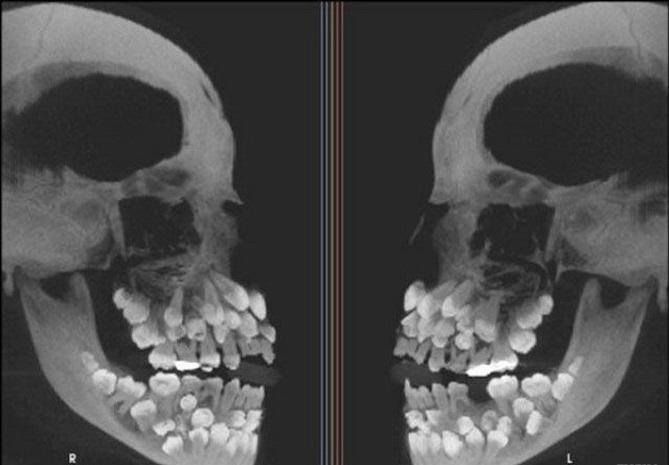

Zdjęcie rentgenowskie czaszki osoby cierpiącej na hiperdoncję (zęby nadliczbowe)

Hiperdoncja, zwiększenie liczby zębów (łac. hyperdontia; z gr. νπερ – zbyt dużo, οδοντ – ząb, -ια; ang. hyperdontia) – zaburzenie rozwojowe polegające na obecności zębów nadliczbowych o nieprawidłowej budowie albo prawidłowo zbudowanych zębów dodatkowych.

W uzębieniu mlecznym hiperdoncję obserwuje się rzadko (0,3-1,8%), w uzębieniu stałym częściej (2-3,1%). Występuje częściej u mężczyzn niż u kobiet (2:1) i częściej dotyczy szczęki niż żuchwy (9:1).